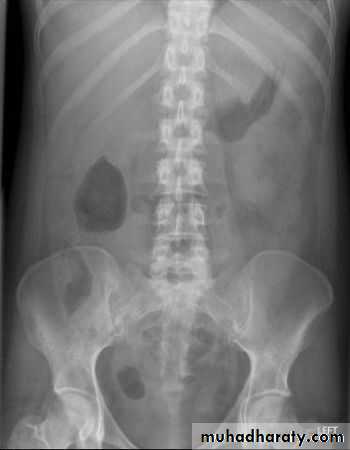

How to look at a plain abdominal film

• Analyze the intestinal gas pattern• Identify any dilated portion of the gastrointestinal tract

• Look for gas outside the lumen of the bowel

• If there are any calcifications, try to locate exactly where they lie

• Assess the size of the liver and spleen

• Look for ascites and soft tissue masses in the abdomen and pelvis